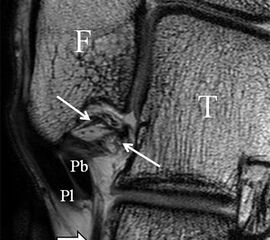

Der Ursprung des Ligamentum fibulocalcaneare liegt unmittelbar kaudal und dorsal des Ursprungs des Ligamentum fibulotalare anterius, so dass gehäuft kombinierte Verletzungen und auch ein gemeinsamer knöcherner Ausriss beobachtet werden. Nach kaudal dorsal verläuft das Band dann nach medial konvex unter die Peroneussehnen. Danach ist ein schräg deszendierender, gestreckter Verlauf bis zum calcanearen Ansatz abgrenzbar (Abb. 10). Dieser zu allen drei Standardebenen schräge Verlauf erschwert häufig die Diagnostik des LFC vor allem bei subtileren Verletzungen. Spezialprojektionen, die dem Bandverlauf orthograd folgen (entweder schräg coronar oder schräg sagittal) erleichtern auch hier die Diagnostik (Abb. 11) insbesondere nicht dislozierter Avulsionen. Assoziierte Verletzungen der Peroneussehnenloge müssen mit beurteilt werden, wobei neben Verletzungen der Sehnen und Sehnenscheiden die Beurteilung des Retinaculum peroneum superius und inferius wichtig ist. In einem Kollektiv von Patienten mit chronischen Außenbandinstabilitäten weisen 50% der Patienten eine Verletzung dieser Strukturen auf 5. Auch hier erleichtern hochauflösende Techniken die Diagnostik (Abb. 12).